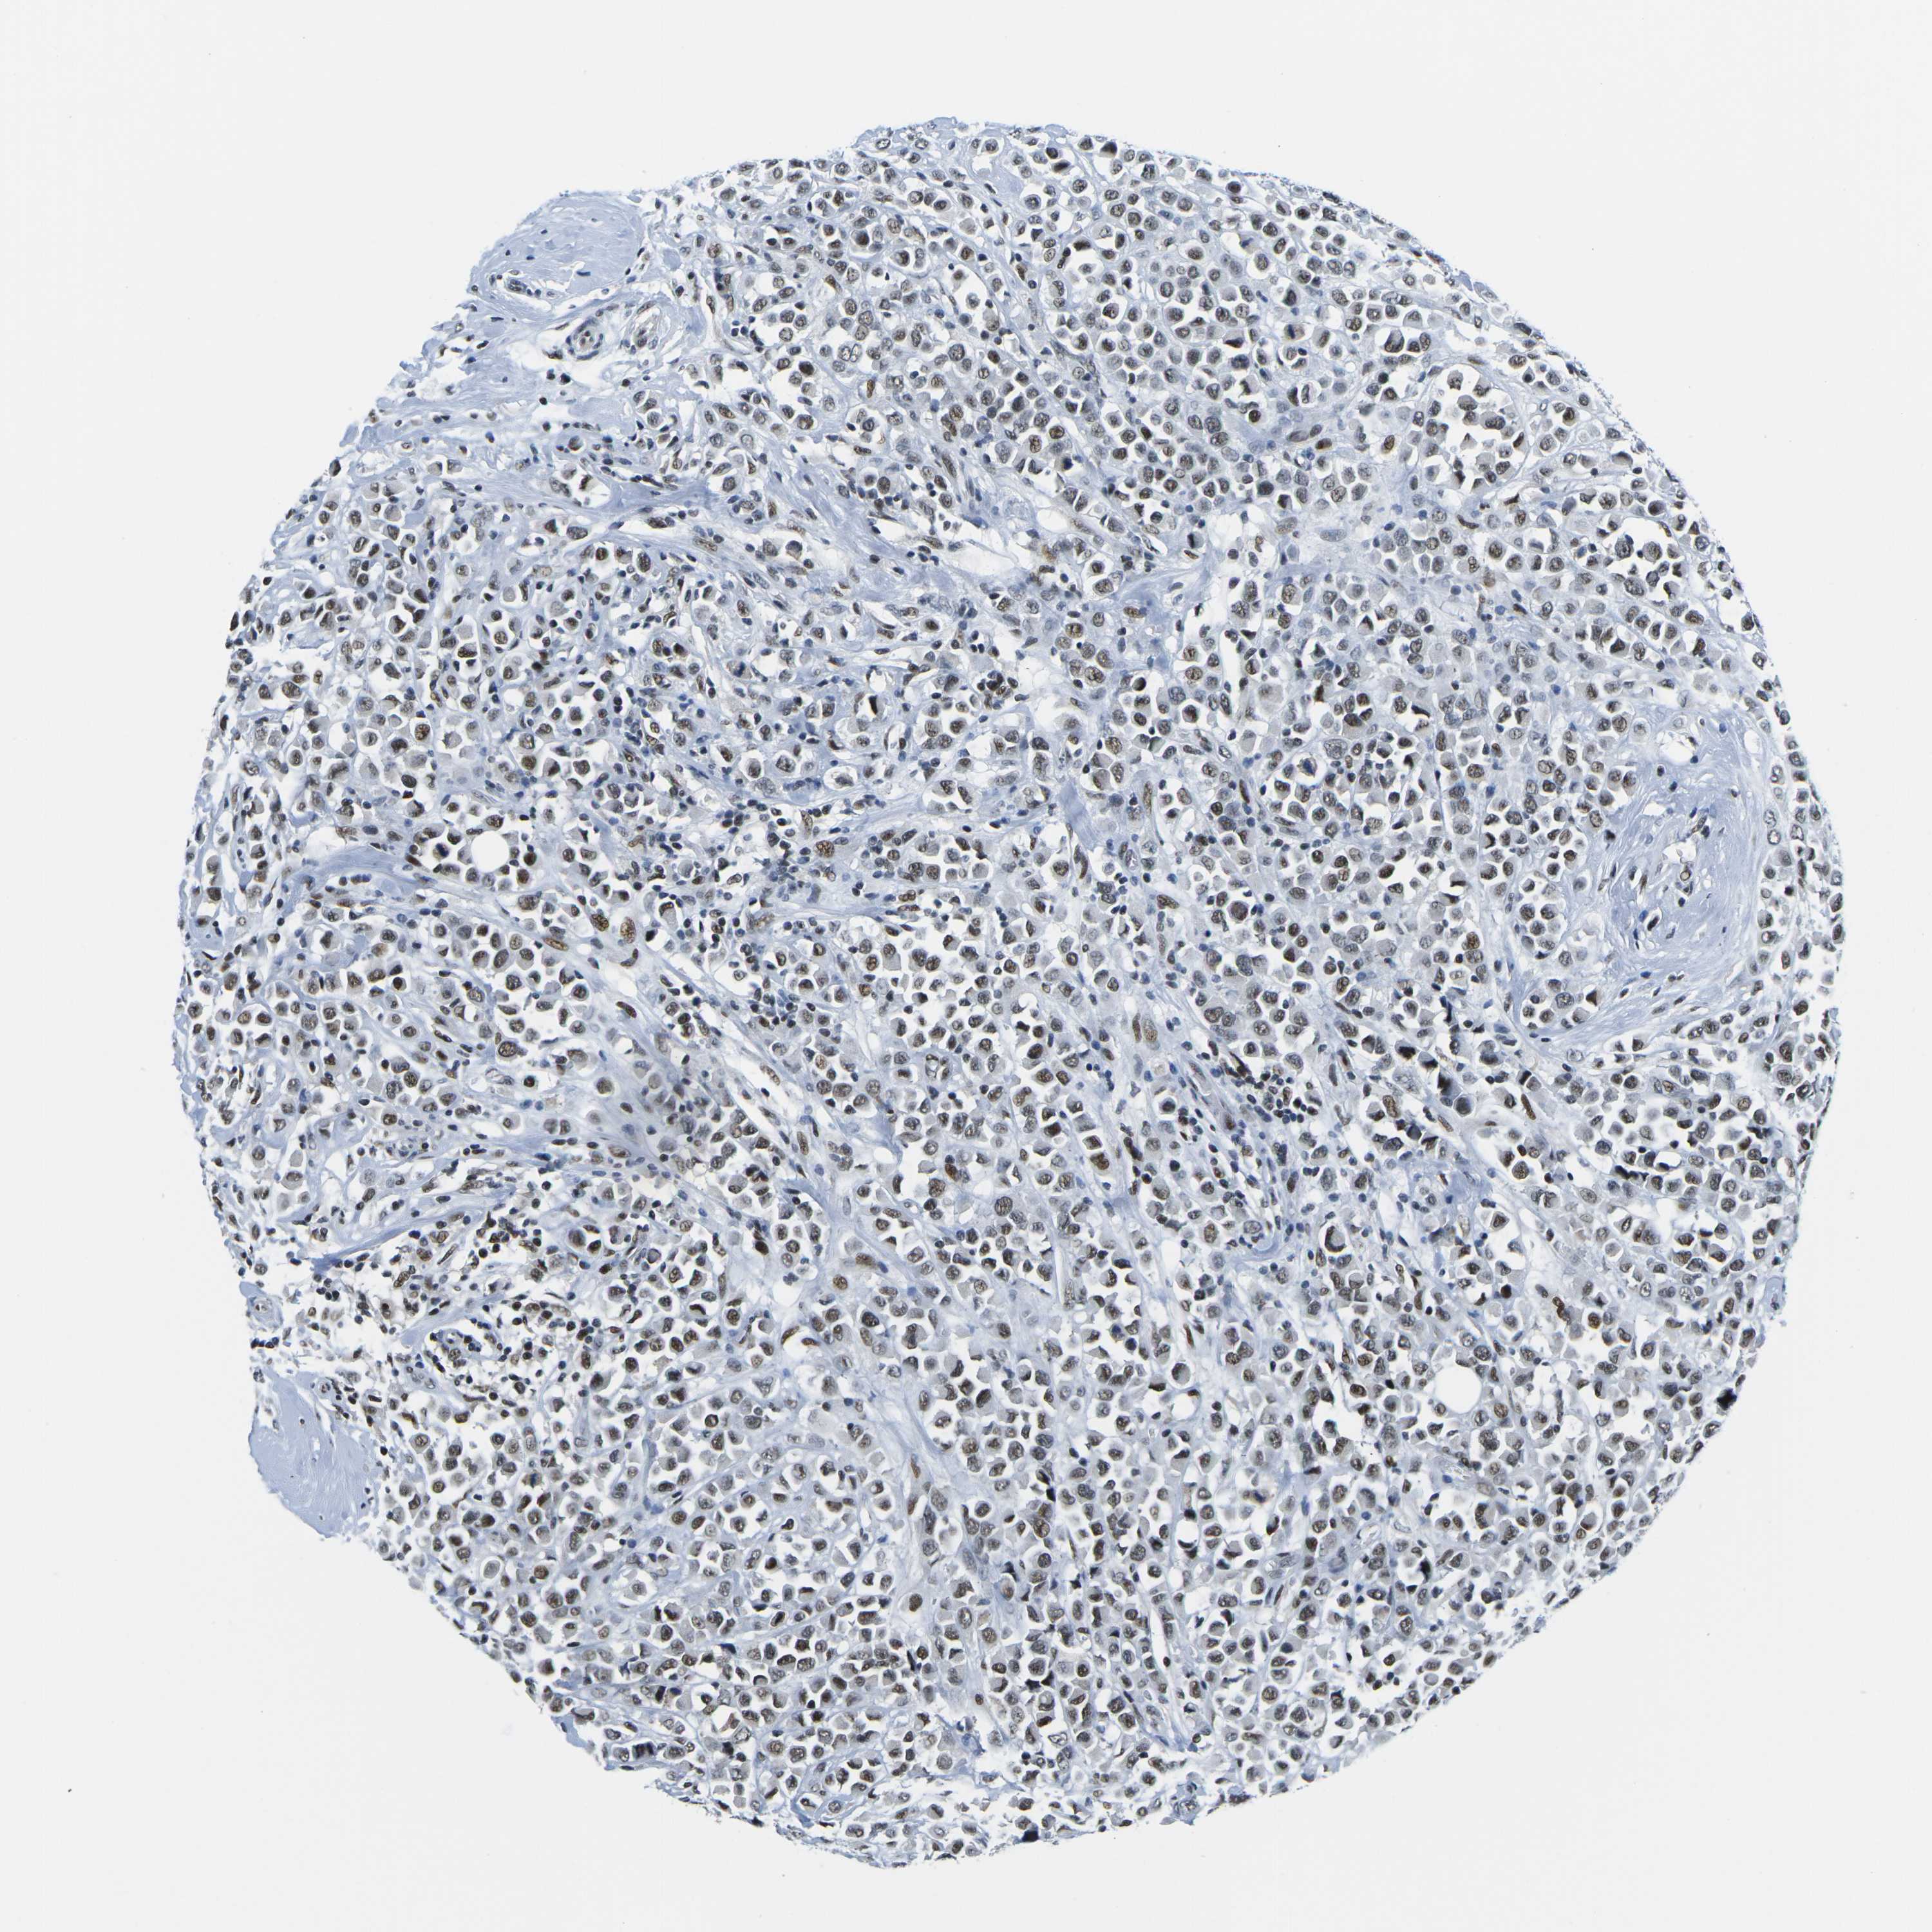

CANCER BREAST CANCER Show tissue menu

BRCA TCGA BRCA VALIDATION PROTEIN EXPRESSION